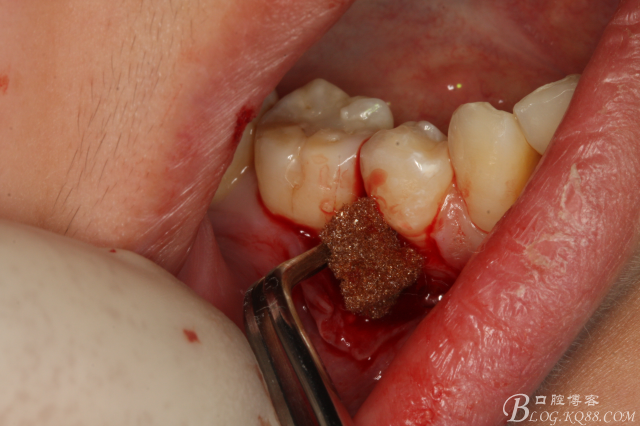

圖18.放膠質(zhì)銀